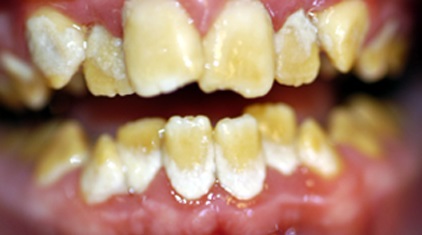

C’est la dentinogénèse imparfaite

, qui était décrite sous le nom de Dysplasie de Capdepont lors de mes études:

Dentinogénèse imparfaite Uninervité de Rennes 1).

Dentinogénèse imparfaite (Uninervité de Rennes 1).